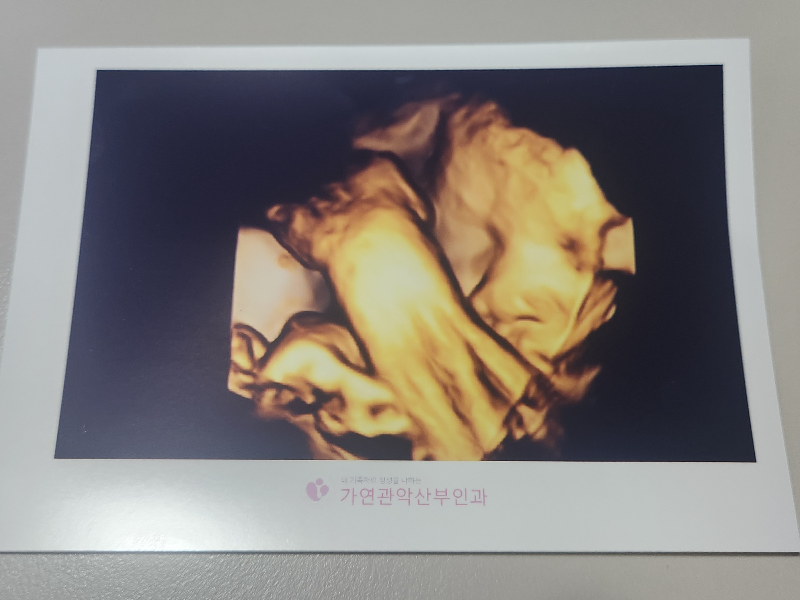

오랜만에 얼굴을 보여준 복덩이입니다.

하지만 다시 팔로 얼른 가리는 복덩이입니다.